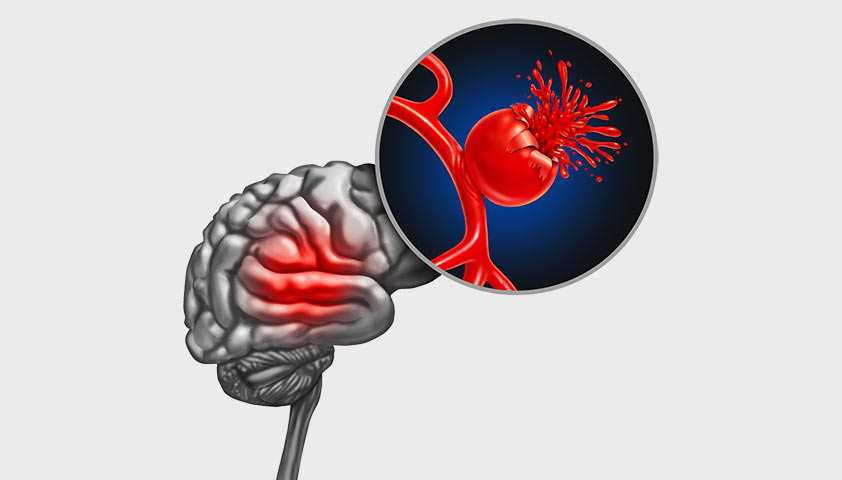

Снимки и иллюстрации микроаневризм сосудов головного мозга